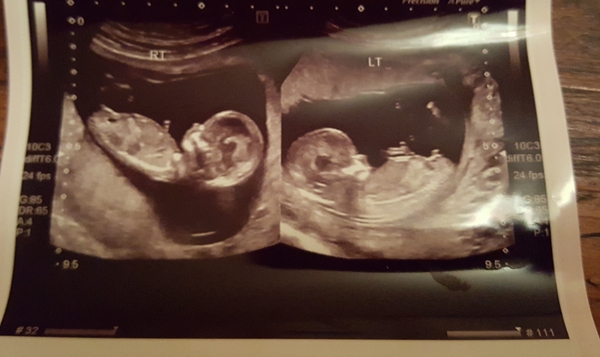

Here is the picture - she took a pic of each twin separately and joined them together - apparently they are now too big to get them nicely together in one shot - i have ones with both in but cant easily make out whats what!

ooo also - by LMP I am 12+5 today. I asked for measurements and she said 65mm and 69mm. Then when I got the report it says 68mm and 73mm - dating 13+3 (yest). I looked at the graph and by the original measurements she gave me I fall into roughly 12+3/4. so the 3-4mm diff between verbal and written measurements puts the due date a week earlier (by ov date EDD is 17th June). This is just a curiosity and I'm fine to go with the final measurements as it means I get to do the next scan in 6 weeks - but I think the first measurements she gave are the correct ones. I was tracking temperature/ovulation and sex and it's unlikely they were conceived a week earlier. Maybe next scan they will even out. But anywho I am just so pleased and grateful they are both growing ok and at the rate expected so far, that theyre not measuring tiny (they might even be big for their age? if second measurements are correct?).